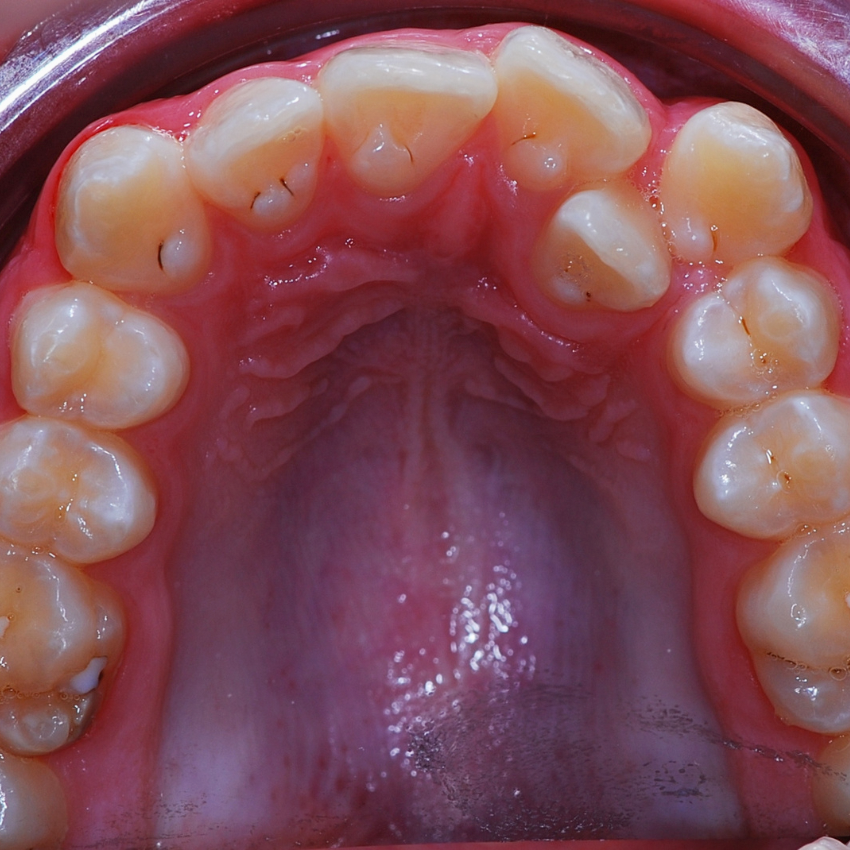

Раннее ортодонтическое лечение действительно не гарантирует, что ребенку не понадобятся брекеты в будущем. Однако пластинки могут быть нужны, потому что некоторые ортодонтические проблемы важно решить в детстве. Вот в каких случаях лучше заранее носить пластинки:

- Если молочный зуб ребенка был удален раньше времени. Нужно установить аппарат, чтобы это место не заняли соседние зубы. Иначе потеря зуба может спровоцировать скученность зубов и даже неправильный прикус.

- Если верхняя челюсть ребенка слишком узкая, зубам не хватает места. Ортодонт может увидеть это у ребенка в шесть-семь лет — с появлением первых постоянных зубов. Установка аппарата в этом возрасте поможет расширить верхнюю челюсть. В более позднем возрасте приходится решать проблему другими путями, например удалением зубов.

Когда ребенок вырастет и станет подростком, ему все равно может понадобиться брекет-система для финишного выравнивания зубов. Однако это лечение будет значительно более простым и быстрым: например, не нужно будет удалять здоровые зубы или делать челюстно-лицевую операцию.

Это не значит, что любому ребенку с неровными зубами нужны ортодонтические аппараты. Если челюсти формируются гармонично, есть место для прорезывания всех зубов, а прикус правильный, то неровное положение зубов лучше корректировать сразу на брекет-системе после прорезывания всех постоянных зубов.

По показаниям брекеты могут использовать и в тех случаях, когда молочные зубы еще не полностью сменились на постоянные.

Например, если у ребенка не хватает места для прорезывания всех зубов. В семь-восемь лет ему можно поставить брекеты, но не на все зубы, а только на четыре передних и два дальних. Между этими брекетами устанавливают пружину, которая расталкивает зубы.